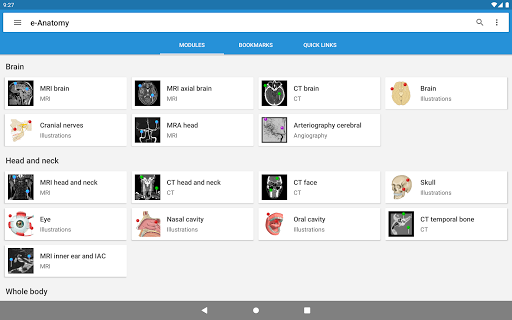

IMAIOS e-Anatomy es un atlas de anatomía humana para médicos, radiólogos, estudiantes de medicina y técnicos en radiología. Echa un vistazo a más de 26 000 imágenes médicas y anatómicas de forma gratuita antes de suscribirte a nuestro detallado atlas de anatomía humana.

e-Anatomy se basa en el galardonado atlas en línea IMAIOS e-Anatomy. Lleva contigo la referencia más completa de anatomía humana, dondequiera que vayas, en tu dispositivo móvil o tableta.

e-Anatomy tiene más de 26 000 imágenes que contienen series de imágenes en vistas axiales, coronales y sagitales, así como radiografías, angiografías, imágenes de disección, gráficos anatómicos e ilustraciones. Todas las imágenes médicas fueron etiquetadas cuidadosamente, más de 967 000 etiquetas disponibles en 12 idiomas, incluida la Terminologia Anatomica latina.

Nuevo: ahora puede filtrar los módulos por región o por tipo de contenido para que pueda encontrar el módulo que busca mucho más rápido.